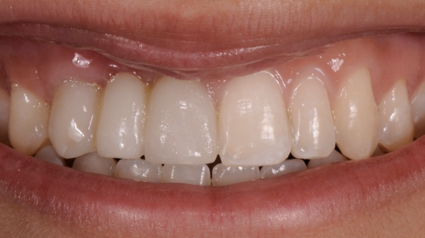

After the 3rd bone graft failed, the patient sought second opinions. She was a college sophomore at the time. Using a combination of interdisciplinary therapies, including S.M.A.R.T. minimally invasive bone grafting, Dr. Ernesto Lee was able to tridimensionally reconstruct this severe defect and place implants to restore the patient’s smile. The S.M.A.R.T. bone graft was also extended to treat adjacent teeth with thin/dehisced bone.

A long-term CAD/CAM fabricated temporary restoration is in place while she finishes medical school at an out-of-state university. The treatment of this case was published in detail in a special issue of the Compendium of Continuing Education in Dentistry, one of the largest circulation journals in our profession.